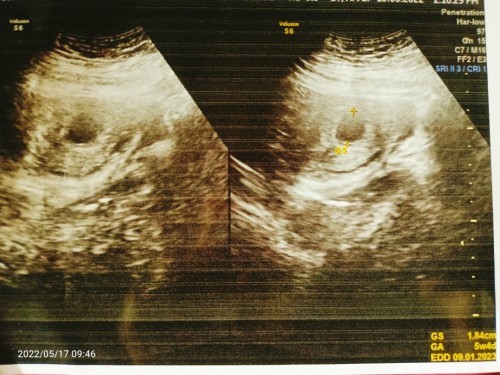

Usia kehamilan sudh 7minggu Pas di USG kantong Masi kosong

Usia kehamilan sudh 7minggu Pas di USG usia 5minggu , harus nya kata dokter nya usia kehamilan 7minggu itu kantong sudh terlihat janin Tapi ini Masi kosong, Dan disuruh untuk USG 2 Minggu lagi untuk melihat perkembangan nya. Sebelum nya belum pernah USG pas kehamilan 1/2 BLN lantran kemaren keluar flek 2 x maka nya sya sma suami sepakat coba periksa ,tapi hasil nya gitu Mohon saran nya dong Bun, mana tau ada yg ngalamin kayak sya ini 🙏 #seriusnanya #bantusharing #ingintahu #pleasehelp